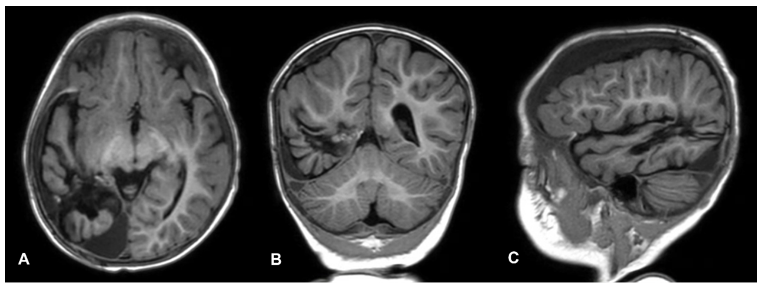

Infantile High-Grade Glioma : A Case Report from Southern Thailand

Rachakorn Punyasiri, Avika Trakulpanitkit, Thara Tunthanathip

22-29